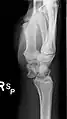

![]() The left lunate bone | |

Bone

The proximal surface of the lunate bone is smooth and convex, articulating with the radius. The lateral surface is flat and narrow, with a crescentic facet for articulation with the scaphoid bone. The medial surface possesses a smooth and quadrilateral facet for articulation with the triquetral bone. The palmar surface is rough, as is the dorsal surface. The dorsal surface is broad and rounded. The distal surface of the bone is deep and concave.[4]